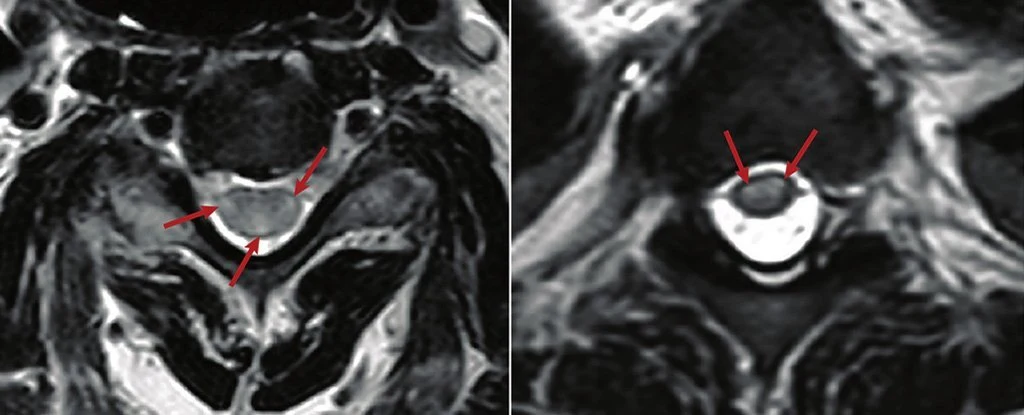

Ostre poprzeczne zapalenie rdzenia kręgowego (ATM) to zapalenie rdzenia kręgowego, które może powodować ból, paraliż i problemy sensoryczne. Zostało ono zidentyfikowane u 43 dorosłych z COVID-19 w 21 krajach, z wiekiem pacjentów od 21 do 73 lat, a także u trojga dzieci, w wieku od 3 do 14 lat.